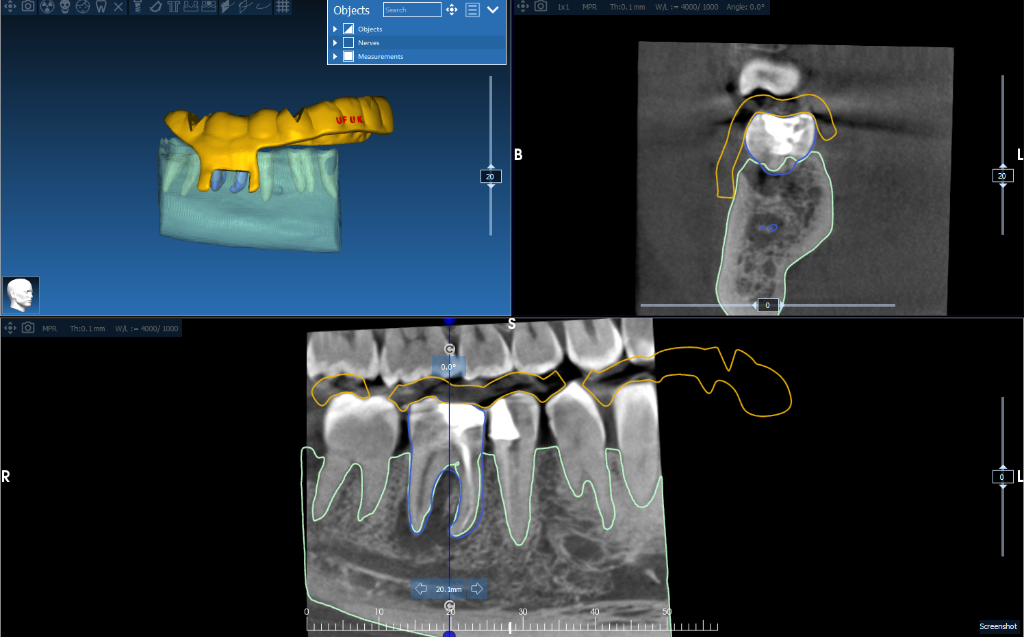

Segmentation Services

CBCT segmentation into clean STL models of nerves, teeth, and bone for diagnostics and surgical planning.